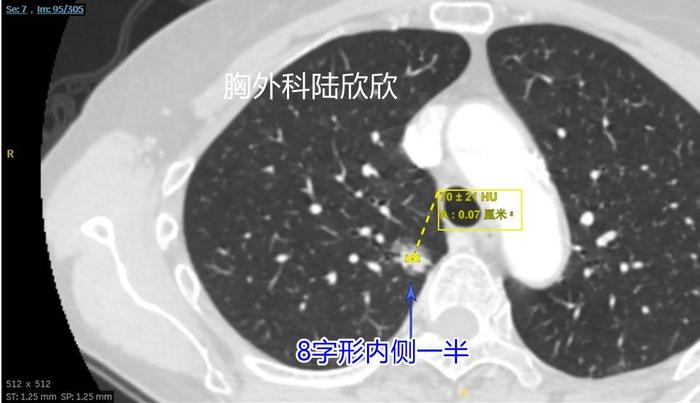

上面两张图,往下至薄层CT的95层面,可见右上肺混合磨玻璃结节的内侧半,是这个8字形磨玻璃结节的内侧半。在这个平面以实性成分为主磨玻璃成分基本上在实性成分周边。在这个层面测量结节大小为15×14毫米,这个测量是错误的。实性成分中心的平均CT值为+70,非常高。